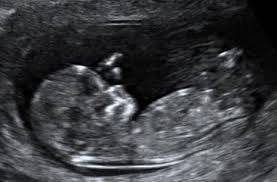

Основите за външните полови органи се образуват и при мъжкия плод пенисът постепенно започва да се вижда. Външните полови белези все още не могат да се различат при ехография, но във вътрешността на тялото вече всичко е определено. При момиченцата са образувани яйчниците, яйчниковите тръби и каналът на матката и вагината. При момченцата тестисите вече са зад коремната стена.   При първата ехография вашият лекар би могъл да определи кога е започнала бременността. Така ще научите относително точно (с разлика не повече от три дни) предвиждания термин за раждането на детето си. От сега трябва да знаете, че раждането може да настъпи две или дори три седмици по-късно и да не се вълнувате излишно, ако има разминавания с прогнозата. В случай, че когато терминът ви настъпи искате да си спестите досадния въпрос : „Не роди ли вече?”, още в началото кажете на близки и познати по-късна дата.

Придружихте ли бъдещата мама на ехографския преглед. Ако не сте, то следващия път задължително го направете. Ще видите как изглежда бебето в утробата и ще чуете забързаният ритъм на сърчицето му.